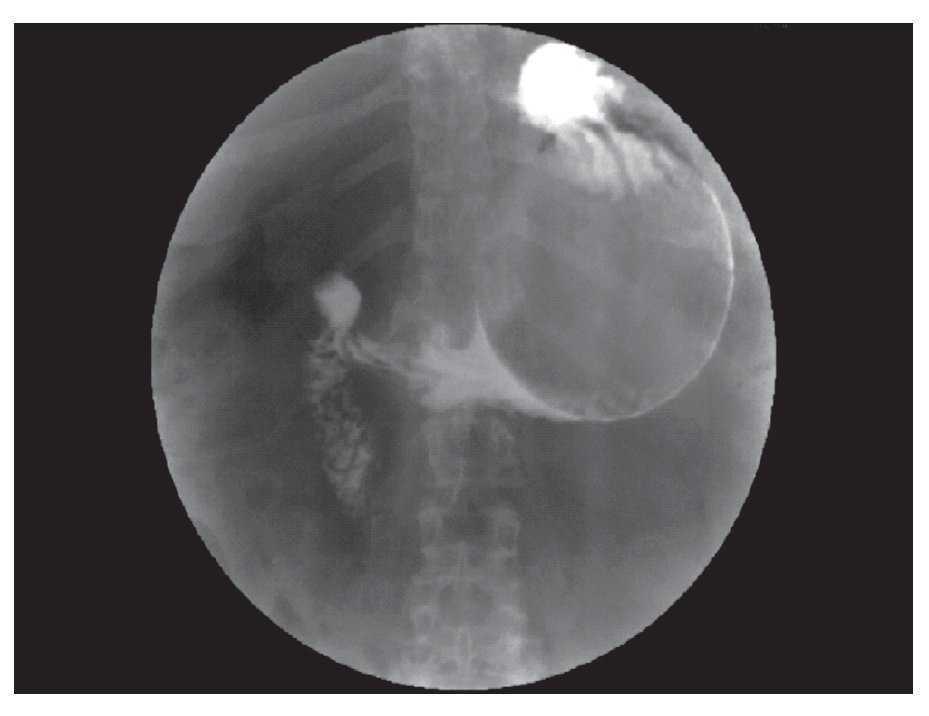

¿ Figura 3. Water-soluble swallow. This study was not capable to show the gastric perforation.

A 54 years old woman with obesity with a body mass index (BMI) of 31.2 was seen by a Gastroenterologist for endoscopic placement of an intragastric balloon (IGB) for weight loss. The patient had a history of well-controlled hypertension and a 15 year history of smoking. She had no history of a known cerebral aneurysm, chronic headaches, use of medications for weight loss, nor a history for familial cranial hemorrhage. By report, the device placement was uneventful, but the same day the patient developed nausea, vomiting and abdominal pain. The pain was persistent and located in the epigastrium. Vomiting was present although the patient was in liquid diet. The patient made strong efforts during vomiting episodes and was traduced in high blood pressure measurements. Four days after the IGB placement, the patient presented to the emergency room (ER) with a severe headache associated to loss of strength and sensation on the lower extremities. The headache had an acute onset of presentation and was after an intense vomiting episode. A cranial-spinal MRI showed findings consistent with a ruptured anterior cerebral artery aneurysm and a subarachnoid hemorrhage (Figure 1). The patient was seen by the Neurosurgery department and an aneurysm clipping was performed without further complications. The patient was discharged from the hospital 5 days after the surgery with tolerance to liquid diet and the use of non-steroideal anti-inflammatory drugs. After hospital discharge, the patient had persistent nausea and vomiting during two weeks and she returned to the emergency room. In addition to these symptoms, the patient presented with somnolence and oliguria. The patient was diagnosed with severe dehydration and acute tubular necrosis. She was transferred to the intensive care unit where she received aggressive fluid replacement and was started on a dopamine drip. Her mental status normalized, but two days after the hospitalization she began complaining of intense abdominal pain and chills. On physical examination, the patient had abdominal diffuse tenderness, hyperestesia and hyperbaralgesia. An abdominal CT showed abundant amount of peritoneal fluid and free intraperitoneal air (Figure 2). A mixture of sodium amidotrizoate and meglumine amidotrizoate in a proportion of 10:66 (Gastrografin®) for an upper gastrointestinal swallow study was performed, but it was not possible to identify a site of perforation (Figure 3). Under the suspicion of gastric perforation secondary to intragastric balloon, wide-spectrum antibiotics were started and the patient was immediately taken to the operating room where a laparoscopic exploration was performed. During surgery, an anterior perforation at the body of the stomach was identified as well as abundant purulent peritoneal liquid (Figure 4). The balloon was deflated by punction and pulled-out of the stomach through the site of perforation. Closure of the perforation was made with a linear laparoscopic stapler and reinforced with continuous non-absorbable suture. An extensive abdominal lavage was done. The patient was transferred to the ICU due to a significant systemic inflammatory response and septic shock. Although the patient required fluid supplementation postoperatively, the patient remained stable, was extubated on postoperative day 4 and further hospital course was uneventful. The patient was discharged from the hospital two weeks after the operation ambulatory and tolerating a general diet. At a 6-month follow up the patient is asymptomatic and without neurologic deficits or gastrointestinal symptoms.